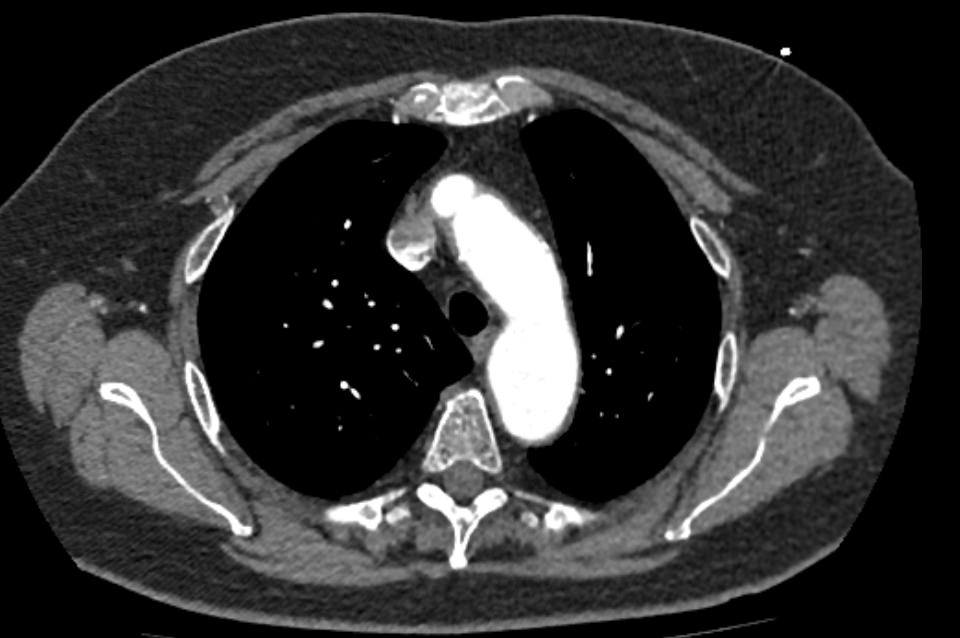

Одним из информативных методов диагностики сосудистой патологии является мультиспиральная компьютерная томография грудной аорты и ее ветвей (КТ-ангиография). Метод сканирования при помощи рентгеновских лучей и цифровой обработки данных позволяет получать послойные снимки сосудов и трехмерные реконструкции сосудистой системы в мельчайших подробностях.

Для того, чтобы качественно визуализировать сосудистую систему КТ-ангиография предусматривает в обязательном порядке применение контрастного усиления. Йодсодержащее контрастное вещество вводится пациенту внутривенно и, благодаря способности контраста поглощать рентгеновские лучи, ярко контрастирует сосудистую систему на фоне окружающих тканей.

КТ-ангиография позволяет диагностировать аневризмы аорты, сосудистые аномалии развития, воспалительные изменения стенок сосудов, пристеночные тромбы, сужения просвета сосудов за счет сдавления извне близлежащими опухолевыми образованиями.

В медицинских центрах «Доступная медицина» КТ сканирование грудной аорты и ее ветвей проводится на новейших мультиспиральных компьютерных томографах экспертного уровня TOSHIBA AQUILION. Современные технологии мультисрезового сканирования обеспечивают высокое качество изображений при уменьшенной дозе облучения для пациента. Это делает КТ-ангиографию высокоинформативным быстрым методом диагностики сосудистой патологии. Процедура не требует вмешательства в организм пациента и может проводится для скринингового обследования с целью раннего выявления патологии грудного отдела аорты.